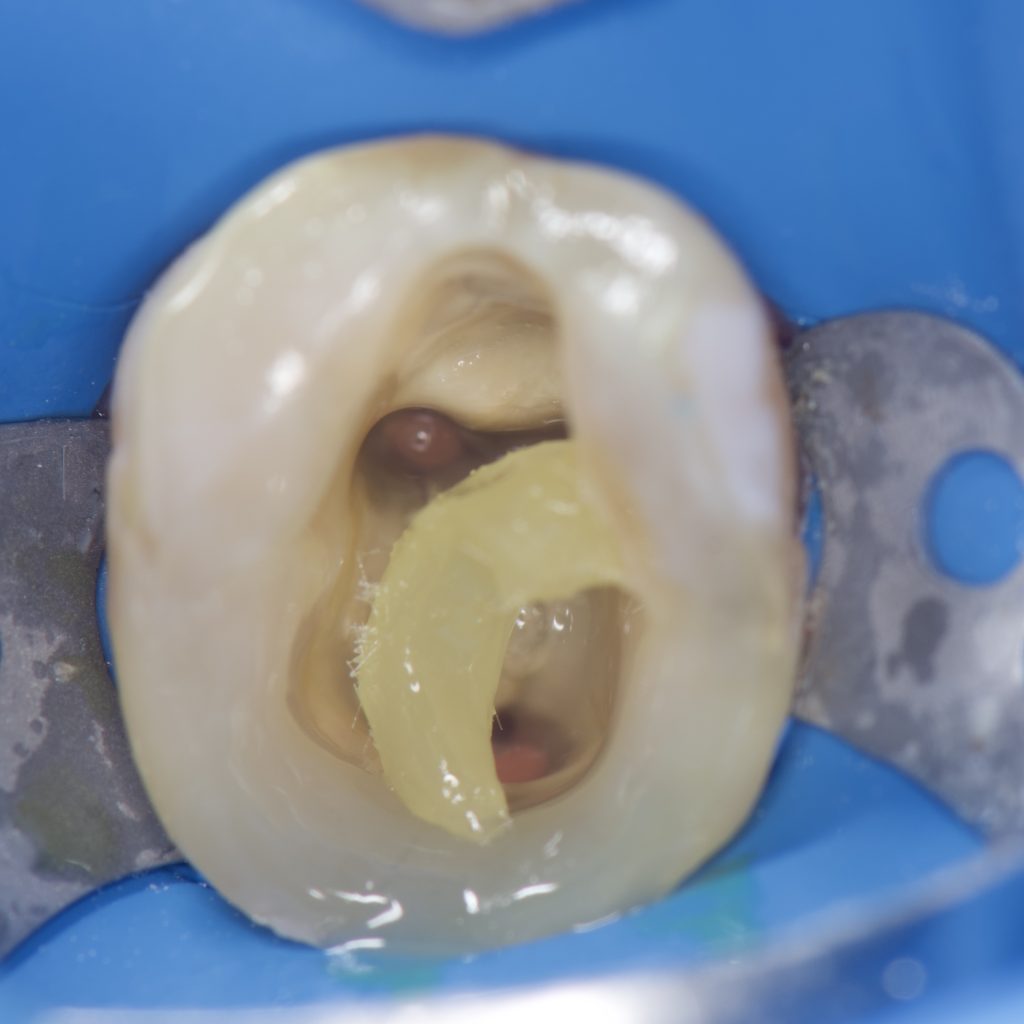

– Deep margin elevation done with gold standard Bond and Ap-x composite

– Endodontic Re-treatment done, Obturation with Bioceramic Sealer and single cone